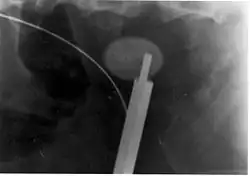

Ureteroscopic surgery

Ureteroscopy has become increasingly popular as flexible and rigid fiberoptic ureteroscopes have become smaller. One ureteroscopic technique involves the placement of a ureteral stent (a small tube extending from the bladder, up the ureter and into the kidney) to provide immediate relief of an obstructed kidney. Stent placement can be useful for saving a kidney at risk for postrenal acute kidney failure due to the increased hydrostatic pressure, swelling and infection (pyelonephritis and pyonephrosis) caused by an obstructing stone. Ureteral stents vary in length from 24 to 30 cm (9.4 to 11.8 in) and most have a shape commonly referred to as a "double-J" or "double pigtail", because of the curl at both ends. They are designed to allow urine to flow past an obstruction in the ureter. They may be retained in the ureter for days to weeks as infections resolve and as stones are dissolved or fragmented by ESWL or by some other treatment. The stents dilate the ureters, which can facilitate instrumentation, and they also provide a clear landmark to aid in the visualization of the ureters and any associated stones on radiographic examinations. The presence of indwelling ureteral stents may cause minimal to moderate discomfort, frequency or urgency incontinence, and infection, which in general resolves on removal. Most ureteral stents can be removed cystoscopically during an office visit under topical anesthesia after resolution of urolithiasis.[116] Research is currently uncertain if placing a temporary stent during ureteroscopy leads to different outcomes than not placing a stent in terms of number of hospital visits for post operative problems, short or long term pain, need for narcotic pain medication, risk of UTI, need for a repeat procedure or narrowing of the ureter from scarring.[117]